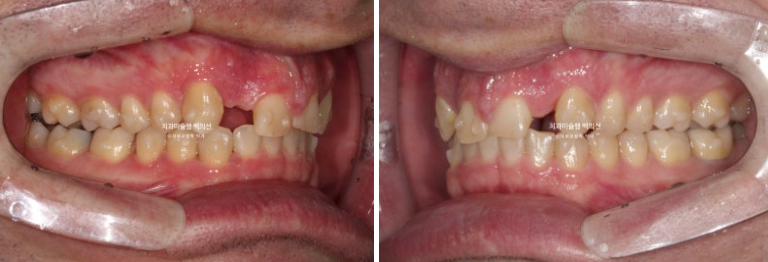

이제 전 후 비교 보겠습니다.

치료기간은 1년 9개월, 재발된 앞니 치축을 바로 잡는데는 4개월이 걸렸습니다.

23.01~25.09

사랑니까지 잘 배열이 되었습니다.

깔끔해진 미소

입매는 잘 유지가 되었습니다.

결손치의 치료방법은 이렇게 초진 시 안모와 돌출 여부에 따라 천차 만별입니다.

결손치나 벌어짐으로 교정치료를 고민 중인 분들에게 도움이 되길 바랍니다.